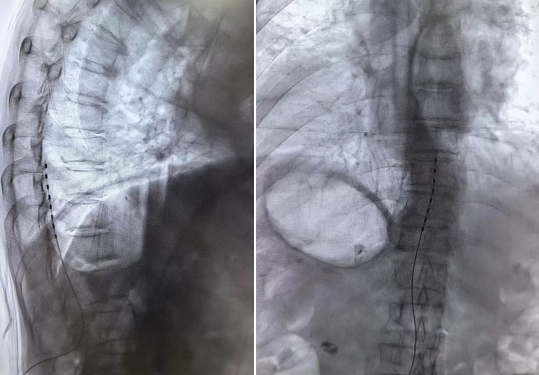

术中,手术团队面临严峻挑战:患者因脊柱后凸导致胸椎小关节内聚增生,几乎完全占据了电极植入的理想位置。凭借丰富的临床经验和精准的影像分析,团队创新性地采用了上下两极锚定技术。这一方案不仅有效解决了特殊解剖结构下单电极易移位的技术难题,还通过方案优化显著降低了医疗耗材费用。

电极测试结果显示刺激覆盖范围精准到位,效果超出预期。术后效果显著:仅24小时,患者疼痛评分便从8分降至4分,原本冰凉的下肢逐渐回暖,患肢皮温升至34.2℃,提示下肢侧枝循环成功重建。为巩固疗效,术后第3天,团队在CT精准引导下为患者实施了腰交感神经节射频消融术,进一步改善下肢血供。经系统治疗,患者疼痛评分最终稳定在2分,患侧皮温升至与健侧一致的35.8℃,为后续溃疡愈合创造了良好条件。